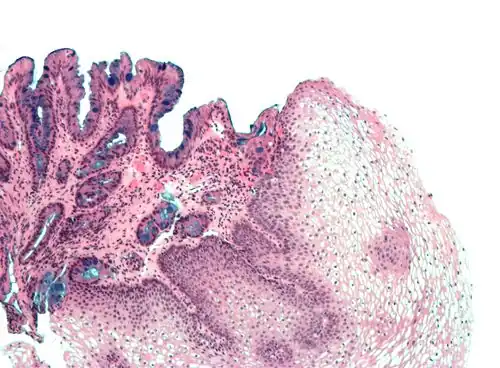

H&E stain of biopsy of normal esophagus showing the stratified squamous cell epithelium.

A stratified squamous epithelium consists of squamous (flattened) epithelial cells arranged in layers upon a basal membrane. Only one layer is in contact with the basement membrane; the other layers adhere to one another to maintain structural integrity. Although this epithelium is referred to as squamous, many cells within the layers may not be flattened; this is due to the convention of naming epithelia according to the cell type at the surface. In the deeper layers, the cells may be columnar or cuboidal.[1] There are no intercellular spaces. This type of epithelium is well suited to areas in the body subject to constant abrasion, as the thickest layers can be sequentially sloughed off and replaced before the basement membrane is exposed. It forms the outermost layer of the skin and the inner lining of the mouth, esophagus and vagina.[2]

Non-keratinized

Non-keratinized surfaces must be kept moist by bodily secretions to prevent them from drying out. Cells of stratum corneum are sometimes without keratin and living.

Examples of non-keratinized stratified squamous epithelium include some parts of the lining of oral cavity, pharynx, conjunctiva of eye, upper one-third esophagus, rectum, vulva, and vagina.[3]